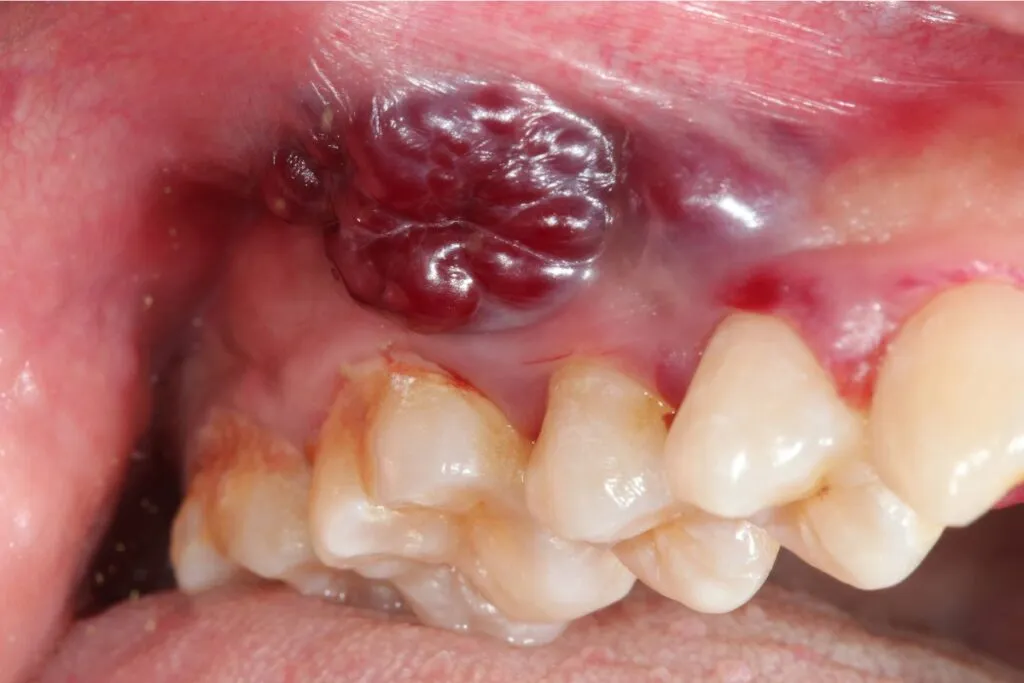

Guzek, zgrubienie, narośl co powinieneś wyczuć językiem lub palcem?

Każde wyczuwalne pod palcami lub językiem zgrubienie, guzek lub narośl w obrębie tkanek miękkich jamy ustnej czy to na policzkach, języku, czy dnie jamy ustnej jest sygnałem alarmowym. Takie nieprawidłowości mogą wskazywać na rozwijający się proces nowotworowy i wymagają poddania się dokładnej diagnostyce.

Asymetria i zmiana koloru subtelne znaki, które zdradza lustro

Podczas samobadania warto zwrócić uwagę na subtelne zmiany. Nietypowe zabarwienie błony śluzowej, na przykład pojawienie się obszarów ciemniejszych lub jaśniejszych niż otaczająca tkanka, może być ważnym sygnałem. Podobnie, wszelkie zauważalne asymetrie w wyglądzie jamy ustnej powinny wzbudzić Twoją czujność.

Rak policzka i dziąseł: na co zwrócić uwagę podczas mycia zębów?

W przypadku raka policzka, zmiany mogą przyjmować postać białych plam, owrzodzeń lub guzków zlokalizowanych po wewnętrznej stronie policzka. Natomiast rak dziąseł objawia się jako wszelkie niegojące się zmiany, guzki czy owrzodzenia w tej okolicy, które mogą być mylone ze stanem zapalnym dziąseł.